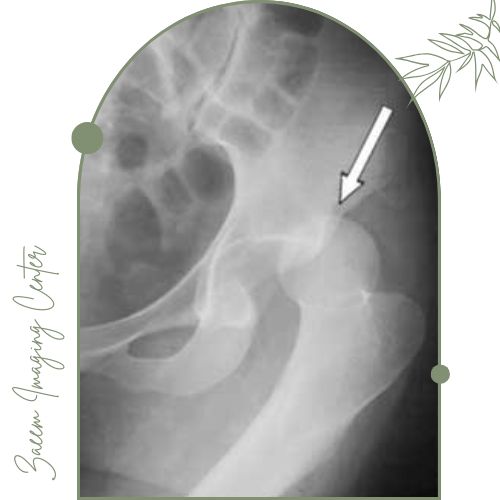

مرکز تصویربرداری پزشکی زعیم تحت مدیریت دکتر علیرضا سرزعیم (فلوشیپ مداخلهای) با همکاری دکتر سمیه زارعی و دکتر مهرناز راسته خدمات تخصصی سونوگرافی مفصل ران نوزاد را براساس جدیدترین پروتکلهای غربالگری و با بهرهگیری از فناوریهای روز ارائه میکند. تیم مجرب این مرکز با استفاده از پیشرفتهترین فناوریهای تصویربرداری مفصل ران نوزاد را با دقت فوقالعاده بالا بررسی میکند تا هرگونه مشکل مادرزادی یا اختلال رشد مانند دررفتگی یا نیمهدررفتگی هیپ در همان ماههای ابتدایی بهدرستی تشخیص داده شود.تجهیزات پیشرفته مرکز

در این مرکز از دستگاههای پیشرفته سونوگرافی مخصوص نوزادان استفاده میشود. این تجهیزات تصویری کاملاً واضحی از ساختار مفصل ران کودک فراهم میکنند و در شناسایی کوچکترین اختلالات یا ناهنجاریهای مادرزادی بسیار موثرند.اطلاعات جمعآوری شده توسط متخصصان با بالاترین استانداردها تحلیل و گزارش میشود تا مادران با اطمینان مراحل غربالگری سلامت حرکتی کودک را طی کنند.